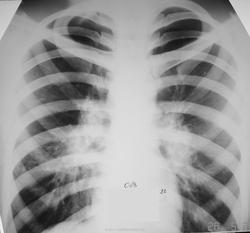

Пациент 22 лет, приехал работать из Средней Азии с намерением работать. Изменения в грудной клетке выявлены при проверочной (профилактической) флюорографии. Последняя флюорография в 2007 году во время службы в Армии. На контрольное обследования не вызывали. Временно проживает у родственников. В течение последних двух недель беспокоит постоянный сухой кашель, слабость. Объективно: пониженного питания, астенического телосложения, кожный покров чистый. В легких дыхание жесткое, единичные сухие хрипы. Тоны сердца ясные. ЧСС-72, АД 110/70 мм.рт.ст. Анализ крови прилагается. С уважением Nikolas

после постановки пробы Манту с 2ТЕ мы воскликнули, "О...." (см. рисунок). Срочно исследовали три пробы промывных вод бронхов на МБТ методом бактериоскопии. МБТ не обнаружили. С уваженим Nik

внутригрудных лимфатических узлов сегодня. Такие формы описаны в период блокады Ленинграда во время ВОВ. Хотел многое написать по этому больному, но не буду коллеги Вас утомлять. Примите к сведению, что такие двусторониие процессы могут быть и в Вашей практике. При бронхоскопии выявлен активный туберкулез в долевых бронхах; в промежуточном бронхе - бронхолимфатический свищ. Посевы бронхиальных смывов дали рост МБТ, чувствительных ко всем противотуберкулезным препаратам. Больной после окончания обследования уехал домой к родителям. Мы сами, в первую очередь, думали о саркоидозе. Спасибо Вам за активное участие. С уважением ко всем Nikolas.